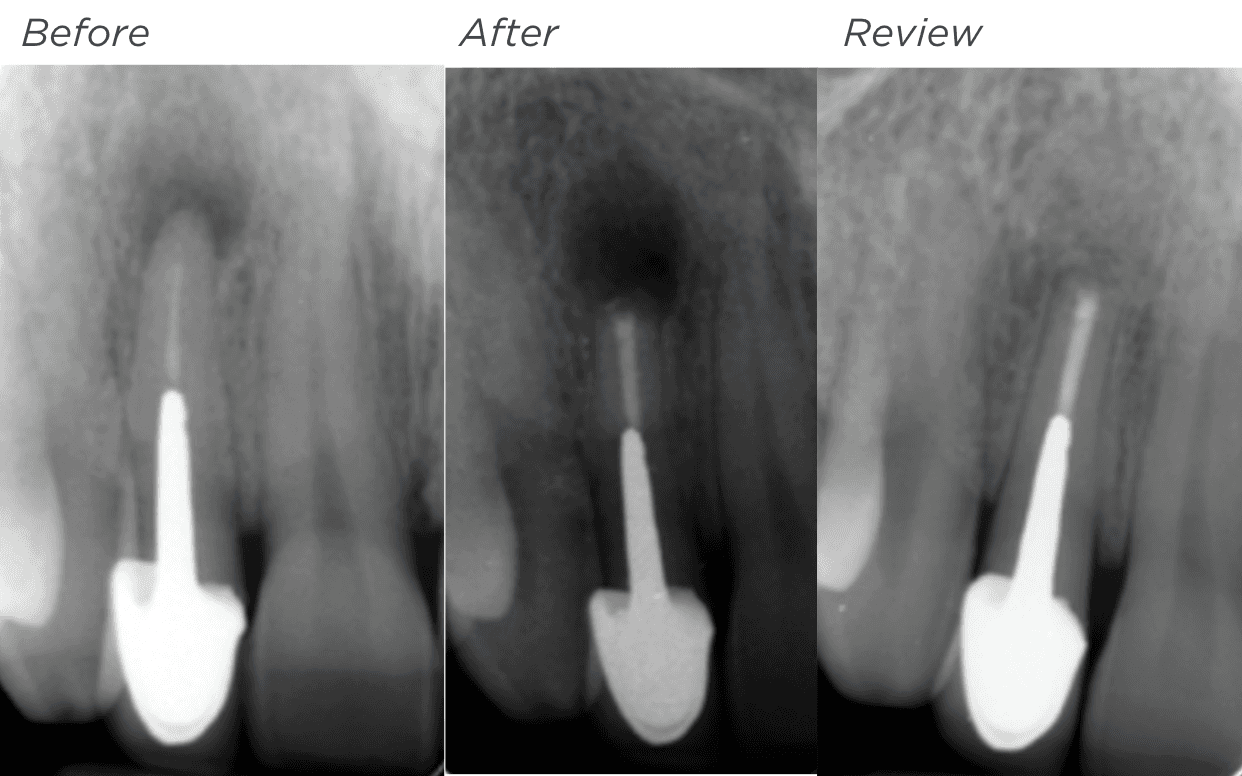

KREENA'S CASES